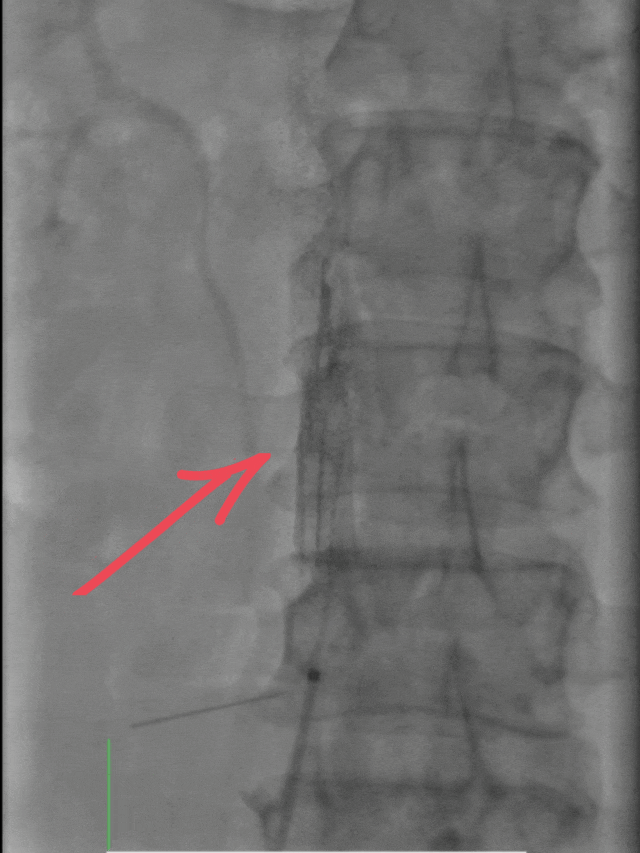

随后置入下腔静脉滤器,如同在血管内筑起“防护网”,有效预防血栓脱落引发更严重的肺栓塞;